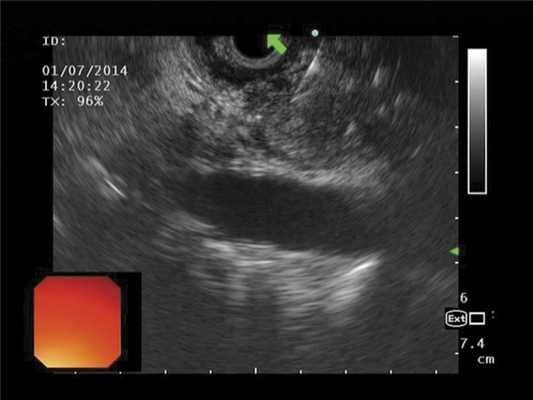

Выполнено ЭУС: УЗ-признаки нарушения желчеоттока на уровне интрапанкреатической части холедоха; признаки компрессии общего желчного и Вирсунгова протока на уровне головки поджелудочной железы (рис. 3). В проекции головки определяется округлое образование с нечеткими контурами до 30 мм в диаметре, пониженной эхогенности. Выполнена ЭУС-тонкоигольная пункция методикой вакуумной аспирации эндоскопической иглой Boston Sсient 22 G.

Рис. 3. Выполнение тонкоигольной пункции образования головки поджелудочной железы иглой Boston Scientific диаметром 22 G, под контролем конвексного ультразвукового эндоскопа Олимпус GE-UCT 140.